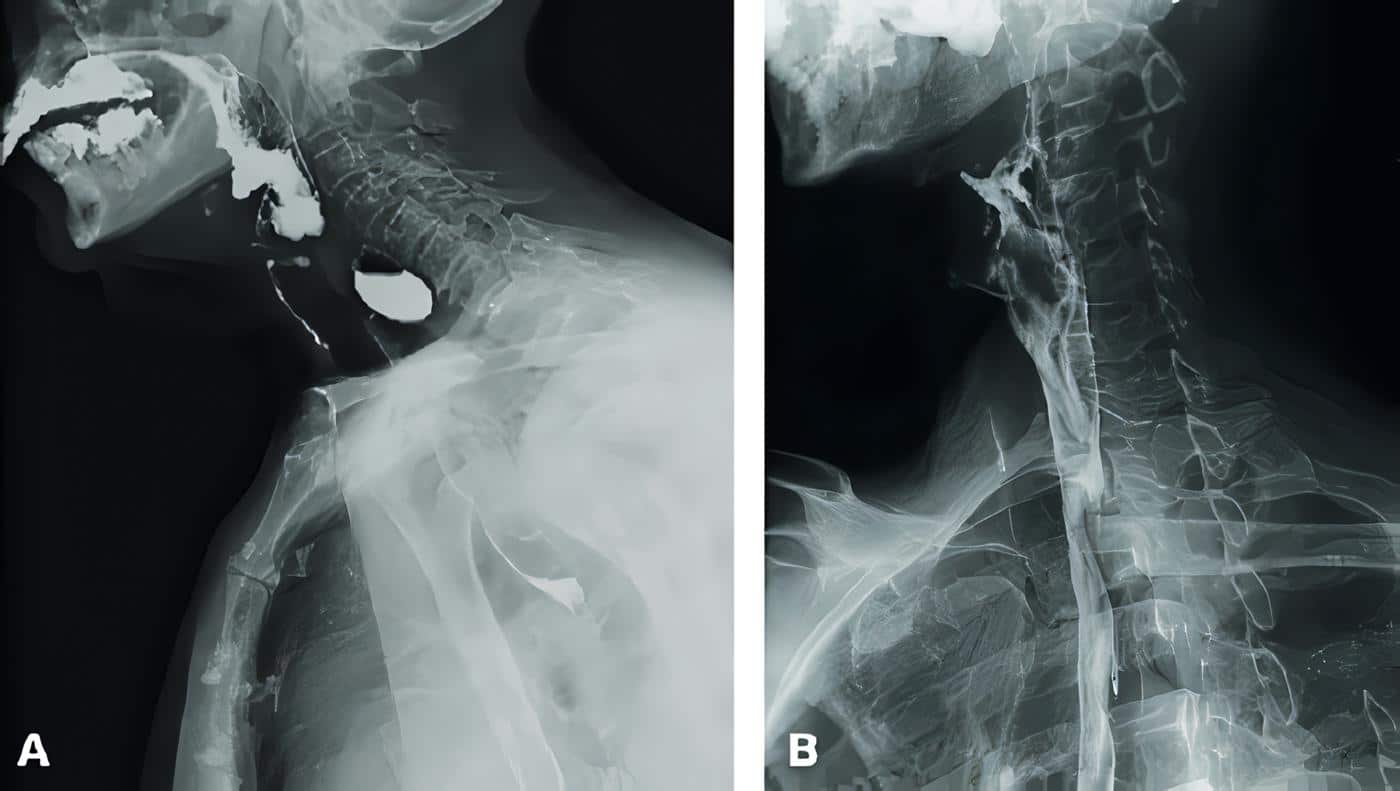

Hubo resolución de los síntomas en todos los pacientes, confirmándose la septotomía completa del tabique por esofagograma y endoscopia en la mayoría de ellos (figura 2). No se presentaron casos de recurrencia y ningún paciente ha requerido reintervenciones.

Figura 2. A, Esofagograma preoperatorio. B, Esofagograma posoperatorio.Fuente: elaboración propia